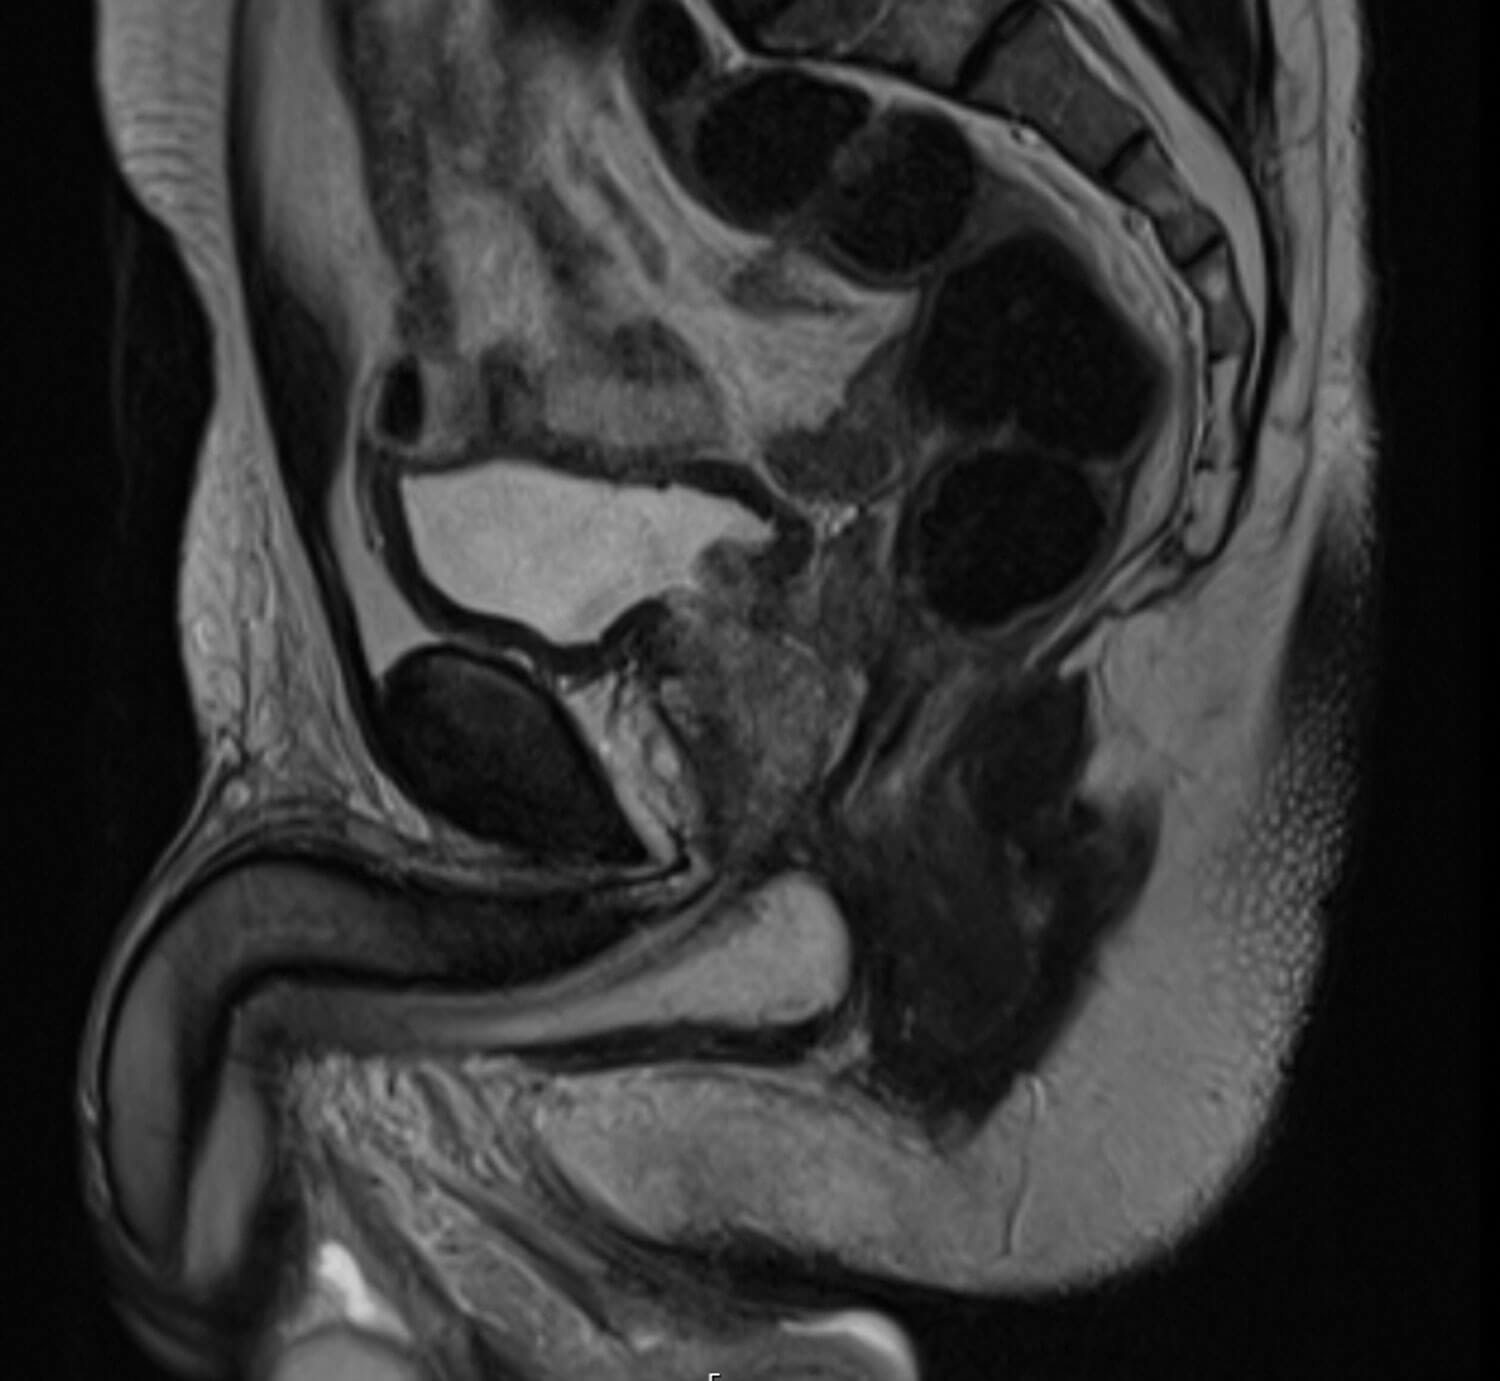

Figure 1: T2 weighted sagittal MRI of the prostate gland demonstrating the anterior tumour.

Annual bi-parametric prostate MRI did not show evidence of progression for another four years. Serial PSA measurements however steadily rose to 7.2ng/ml. Up to date MRI imaging demonstrated a lesion in the anterior prostate from the apex to the mid gland (Figure 1) and further biopsies were recommended revealing adenocarcinoma in 9/27 cores, Gleason grade 4+3=7 (ISUP grade 3) and perineural invasion in the left posterior gland.